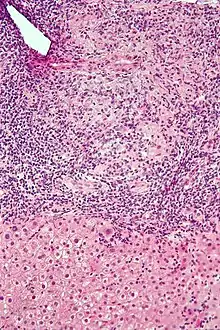

| Micrograph of PBC showing bile duct inflammation and injury, H&E stain | |

On microscopic examination of liver biopsy specimens, PBC is characterized by chronic, nonsuppurative inflammation, which surrounds and destroys interlobular and septal bile ducts. These histopathologic findings in primary biliary cholangitis include:[31]

- Inflammation of the bile ducts, characterized by intraepithelial lymphocytes

- Periductal epithelioid granulomas.

- Proliferation of bile ductules

- Fibrosis (scarring)